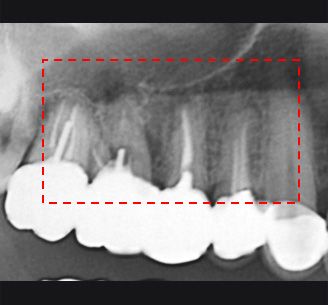

1년전 다른 치과에서 보철치료를 받은 부위에 지속적인 통증과 잇몸 염증으로 내원, 기존 보철물 수복시 신경관을 제대로 치료하지 못하여 염증이

재발된 상황이었습니다. 고운미소에서는 기존 포스트를 제거하고 오염된 부위에 약재를 삽입하여 염증을 제거하는 신경치료를 시행하였습니다.

지속적인 통증과 잇몸염증

기존 포스트 제거 후 근관내 약재 삽입